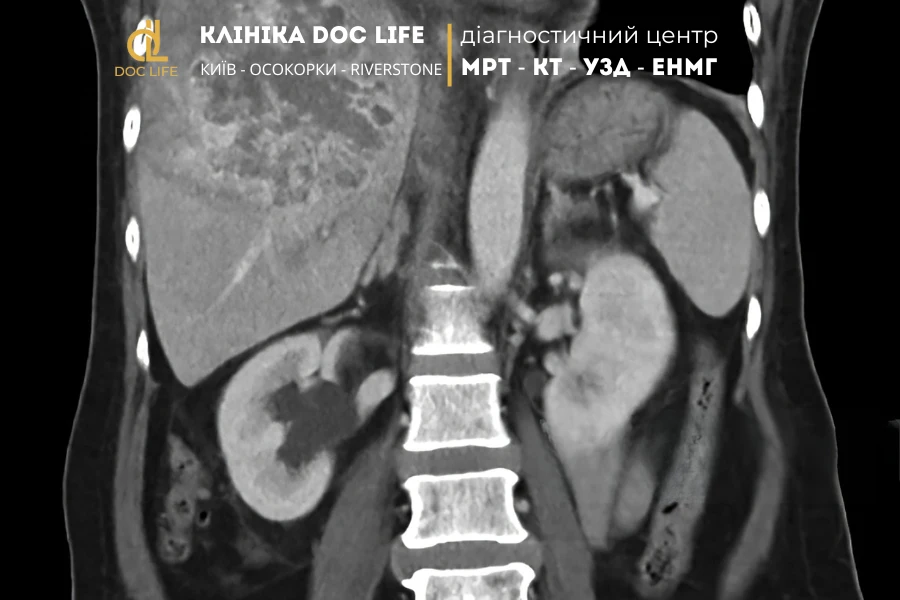

МРТ печінки з контрастом: діагностика метастазів та пухлин

На ранніх етапах захворювання може не проявлятися жодними симптомами — біль, втома або жовтяниця з’являються вже при значному ураженні тканин. Саме тому МРТ печінки з контрастом відіграє вирішальну роль у ранній діагностиці раку. Завдяки високій чутливості методу можна виявити навіть невеликі новоутворення чи метастази, які ще не видно на УЗД або КТ.

МРТ органів черевної порожнини з контрастом призначають тоді, коли є підозра на патологічні зміни, які не можна точно оцінити за допомогою ультразвукового чи навіть комп’ютерного дослідження. Зазвичай пацієнта направляють на таке обстеження після первинного огляду терапевта, гастроентеролога або онколога, коли результати аналізів чи інші методи візуалізації викликають сумніви.

МРТ печінки з контрастом дає змогу з високою точністю розрізняти різні види пухлин — як злоякісні, так і доброякісні. Як зазначає онколог Євгеній Гірагосов: “Завдяки введенню контрастної речовини лікар бачить не лише форму та розміри утворення, а й особливості його кровопостачання, структури й динаміки накопичення препарату. Це дозволяє диференціювати тип пухлини печінки без необхідності інвазивних процедур”.

Метастатичні ураження печінки

Таким чином, МРТ печінки з контрастом дозволяє побачити широкий спектр пухлин — від небезпечних форм раку до доброякісних утворень, які не несуть загрози життю. Завдяки характерним ознакам накопичення контрасту лікар може визначити природу новоутворення, стадію захворювання та вибрати оптимальну тактику лікування без потреби в біопсії.

Медичний центр DocLife надає можливість пройти МРТ у Києві на сучасному магнітному томографі Siemens Sempra 1.5. Діагностика метастазів та пухлин печінки відбувається з використанням двох видів найкращих контрастів німецького виробництва – Гадовіст та Примовіст.